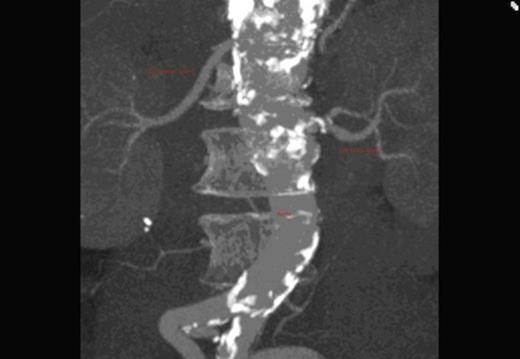

A CT scan revealed an aneurysmal distal thoracic aorta measuring 40mm and 49mm at the level of the diaphragm and of normal calibre at the left renal artery. The right renal artery very interestingly had its origin from the coeliac axis with no significant renal artery disease and the left renal artery showed calcific disease with post-stenotic dilatation at its ostium from the aorta. There were also no accessory renal vessels noted.